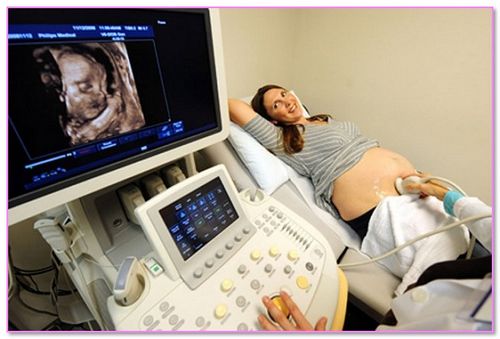

Ще однією відмінною особливістю однояйцевих близнюків буде їхня стать, ці малюки завжди народжуються одностатевими. На даний момент фахівці висунули версію, що найбільше багатоплідної вагітності схильні жінки вік яких на момент першої вагітності більше 35 років. Діагностувати двійню можна вже до кінця першого триместру, навіть на початку можна вже виявити первинна ознака багатоплідної вагітності, при двійні матка значно відрізняється в розмірах від звичайної вагітності. Найкраще виявити факт багатоплідної вагітності допоможе ультразвукове узі, яке зазвичай проводять в останній місяць першого триместру.

- ультразвукове дослідження,

Але все таки варто сказати, що самостійно ставити собі діагноз не варто, це з першого разу не завжди під силу, навіть спеціальному обладнанню. Визначити багатоплідної вагітність найбільше можливо приблизно на восьмий тижні, коли ви робите ультразвукове дослідження.